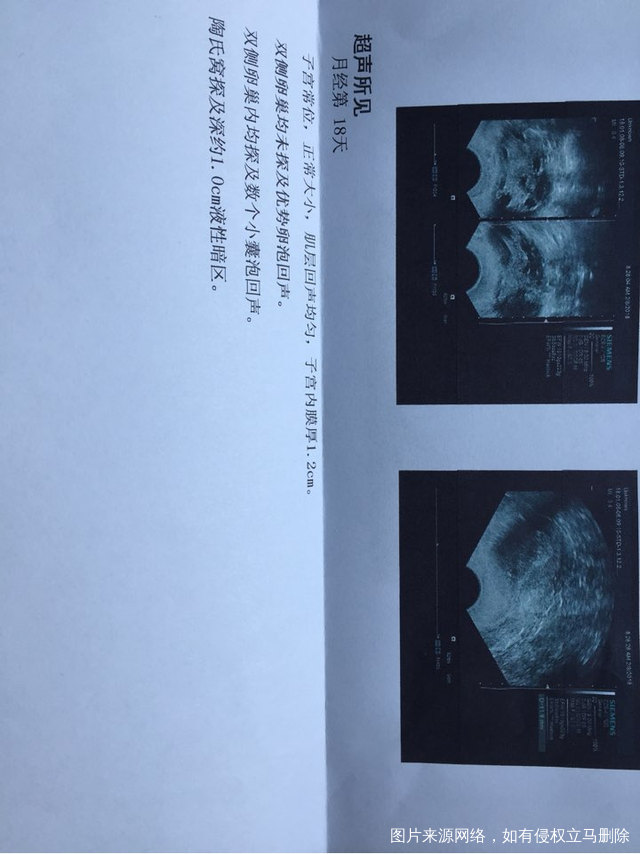

急在线等麻烦医生解答一下谢谢本人38岁备孕中

您好,从您的抽血激素六项看来,促卵泡生成素单项以及该值与促黄体生成素比值分析,结合您的AMH值,您目前的卵巢储备功能不太好,自然怀孕可能性偏小,以及怀孕后流产机会也偏大。平时注意不熬夜,戒烟酒,先试试三到六个月,不行就建议试管